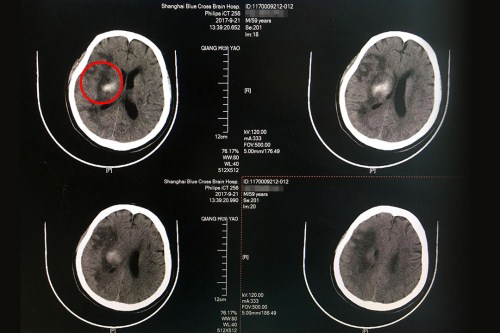

術(shù)前CT:右側(cè)基底節(jié)區(qū)大量出血,血腫破入腦室系統(tǒng),右側(cè)高顱壓。

術(shù)后CT:右側(cè)額顳枕葉梗塞伴右側(cè)基底節(jié)區(qū)出血吸收中,皮層血供再通,較前好轉(zhuǎn)